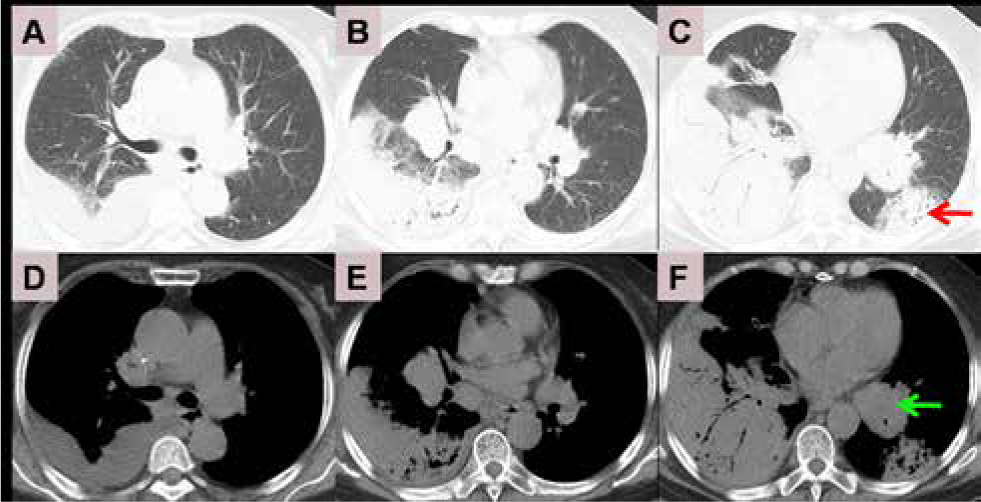

A 71-year-old female was taken to our hospital after experiencing bilateral chest pain and dyspnea for 20 days. She had no other complaints, such as fever, cough and bloody sputum. The patient had a history of arthritis pauperum for 20 years, and denied traditional Chinese medicines for treatment. She had no personal history of smoking and family history of cancer. On clinical examination, no palpable lymph nodes and hepatosplenomegaly were found. There was no obvious rale in bilateral lungs. Computed tomography (CT) of the chest demonstrated a high density shadow in the right middle lower lobe and left lower lobe, and air bronchogram was obvious (Figure 1 C). Bilateral hilar masses exits (Figure 1 E) and low density area was visible (green arrow). Mediastinal lymph nodes enlarged. The crescent shaped liquid density was in right pleura (Figure 1 D). CT of abdomen showed no abnormalities. Bone marrow biopsy showed no infiltration. CT-guided transthoracic core needle biopsy was performed (Figure 2). Pathological section demonstrated diffuse large B cell infiltration in small fibrous tissue. Immunohistochemical staining showed Mum-1(-), Ki-67 index 70%, Cyclin D1(-), CD43(+), CD5(+), Bcl-2(-), CD3(-), CD79a(+), CD23(-), CD10(-), Bcl-6(-), Syn(-), CD20(++), CD56(-) (Figure 3). Based on these findings, PPDLBCL was diagnosed. Due to personal reasons, the patient underwent cyclophosphamide pirarubicin vindesine dexamethasone (CHOP) chemotherapy without rituximab, which was planned to be repeated every 21 days for 6 cycles. Following the administration of 6 cycles of CHOP chemotherapy, chest pain and dyspnea were alleviated. Nevertheless, CT demonstrated bilateral masses and consolidation partially diminished (Figure 4 E F), while a new mass emerged in the right upper lobe (Figure 4 A D blue arrow). Unfortunately, at 9 months of follow-up, the patient died.

Initial chest computed tomography. Lung window: A B C; mediastinal window: D E F. Red arrow indicates reversed halo sign, and green arrow indicates low density area in left hilar mass.

PPDLBCL is extremely rare in primary lung malignant lymphomas. Some case reports and small sample studies delineate the clinical characteristics. Its respiratory symptoms are nonspecific [5]. The key features of CT are single or multiple solid pulmonary nodules or masses, cavitation and mediastinal lymph node enlargement (3, 6 and 7). Consolidation is seldom [5]. In addition to enlarged mediastinal lymph nodes, necrosis in right hilar mass is also visible in this case (Figure 1 F green arrow). Consolidation was obvious. Pathological specimen was from consolidation area (Figure 2), so it indicated that PPDLBCL could cause consolidation. Notably, Marchiori et al reported the reversed halo sign (RHS) can be useful for differentiating invasive pulmonary aspergillosis from pulmonary lymphoma [8]. Nevertheless, we also found RHS in this case (Figure 1 F red arrow). In a word, imaging of PPDLBCL is complex and diverse.